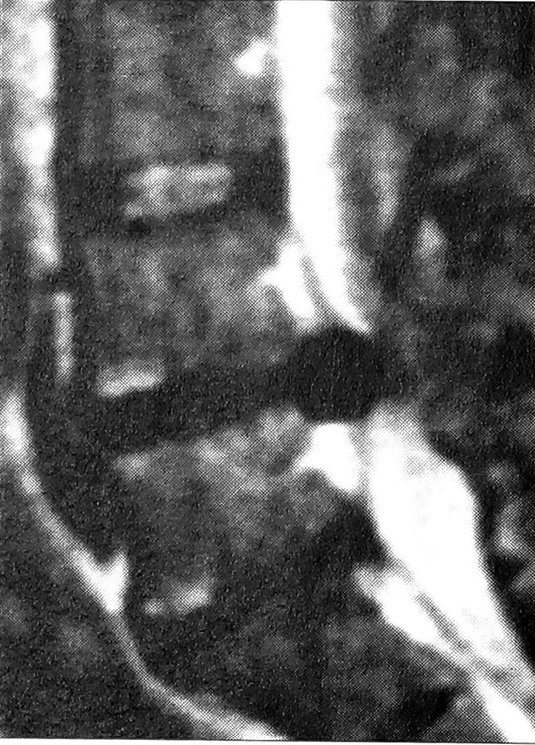

Большинство наших больных поступили с запущенным процессом, длительно леченным консервативно. При магнитно-резонансной томографии выявлены следующие виды поражения диска: протрузия — у 215 больных, экструзия — у 380, секвестрация — у 122 (в том числе внутриканальный секвестр — у 118, внутриоболочечный — у 4). В 96,3% случаев мы обнаружили или значительное выпячивание межпозвонкового диска, вызывающее грубую компрессию корешка, или секвестр (рис. 1), причем у большинства пациентов этот процесс существовал длительное время. Только у 3,7% больных корешковый синдром был вызван небольшой протрузией диска (рис. 2), «подходящей» для применения эндоскопической технологии. У 226 (31,5%) больных имелась сочетанная патология: у 116 — стеноз позвоночного канала (гипертрофия задней продольной, желтых связок), у 38 — спондилолистез I—II степени, у 72 — спаечный процесс (у 49 —вокруг одного корешка, у 19 — внутриканальный, у 4 — внутриоболочечный).

Рис. 1. Секвестрированная грыжа L4-5 (магнитно-резонансная томограмма).

До сих пор остается дискуссионной проблема применения спондилодеза после дискэктомии [17]. Когда мы оперируем пациента с исходно стабильным позвоночным сегментом, спондилодез после микродискэктомии не показан. Однако есть группа больных, у которых до операции выявляются исходная небольшая нестабильность или предрасполагающие к ней изменения в позвоночнике (спондилолиз, spina bifida и т.д.). При выполнении резекции желтой связки и микродискэктомии первичная нестабильность может усугубиться. Кроме того, у молодых пациентов после дискэктомии может произойти уменьшение высоты межпозвонковых промежутков и перегрузка межпозвонковых суставов, что вызовет боли в пояснице в отдаленном периоде. У этих больных приходится, кроме дискэктомии, выполнять стабилизирующие операции одного из трех типов: установка межпозвонковых кейджей с аутокостной крошкой; транспедикулярная фиксация (мы предпочитаем фиксаторы USS /АО/) с межтеловым спондилодезом кейджами с аутокостной крошкой (рис. 3) или материалом cronOS (porous B-tricalcium phosphate granules) фирмы «Mathys»; межтеловой спондилодез аутокостью и фиксатором с термомеханическим эффектом памяти формы, разработанным нашим коллективом [4].

Отдельный вопрос — микрохирургическая дискэктомия при спондилолистезе. Если передний доступ при этой патологии достаточно отработан [2], то в хирургическом лечении задним доступом остается много спорных вопросов. W. Caspar считал, что микродоступ при спондилолистезе противопоказан как трудно выполнимый и приводящий к увеличению смещения. Однако при применении транспедикулярных фиксаторов и межпозвонковых кейджей, имплантируемых из междужкового доступа, мы сочли возможным отказаться от ламинэктомии на одном или даже двух уровнях и использовали малоинвазивные доступы с каждой стороны и на разных уровнях (рис. 4). Такая методика избавляет пациента от вторичной компрессии содержимого позвоночного канала эпидуральным рубцом, образующимся в отдаленные сроки после ламинэктомии.